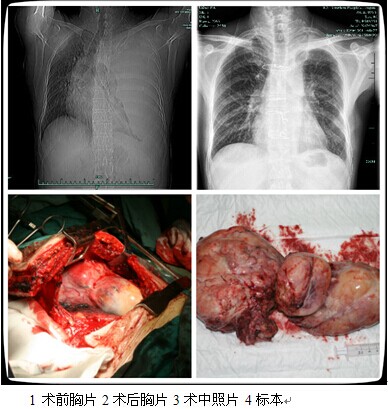

胸外科成功切除罕见胸腔巨大肿瘤

近日,有一位特殊的患者来到了我院胸外科,他的左侧胸腔内长了一个巨大的肿瘤,基本占满了左侧胸腔,左肺已经看不到了,并且心脏大血管也被挤向了右侧胸腔。这位患者姓谢,来自鄞州区,今年59岁,是一位勤劳的农民。5年前在当地医院体检的时候已经发现了左侧胸腔有个肿物,但因病变不大未引起患者的重视。直至3月前,患者开始出现劳作后胸闷气促,并且进行性加重,影响到了正常的劳动,但患者还是没有引起足够的重视,总觉得休息休息就会好。刚好今年有农村体检,老谢在家人催促下去查了一下。这个不查不知道,一查吓一跳,老谢左边的肺看不见了,所以家人赶紧把老谢送到了我院。

经过我院胸外科医生仔细检查,认为老谢得了一种罕见的疾病,称孤立性纤维性肿瘤。对于这种疾病,手术是最好的选择,但因肿块巨大,手术难度非常大,切口的选择、术中失血的控制、左肺的保留等种种难题摆在胸外科医生面前。但为了解除患者的痛苦,经过与其他相关科室专家的讨论,医生为老谢制定了全面而且细致的手术方案,术前准备了自体血以及大量异体血,于8月14日赵子恩主任主刀,江明君副主任、黄科峰主治医生协助下,行“左侧胸腔肿瘤切除术+左肺大疱切除术”,手术过程顺利,并成功保住了患者的左肺。切除的肿瘤有30cm×16cm×8.5cm大小,重量达到2.2公斤。术后患者恢复良好。

据胸外科学科带头人、主刀医师赵子恩主任医师介绍,孤立性纤维瘤(solitary fibrous tumor, SFT)是一种较为罕见的间叶组织来源的肿瘤,生长部位主要见于腹膜后、腔隙及四肢,来自胸部的较为少见,国内文献仅见数例个案报告,能完成这类手术,很好地体现了我院在手术、麻醉以及术后ICU监护等方面的综合实力。